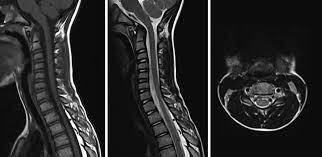

অ্যাকিউট ফ্ল্যাকসিড মাইলাইটিস  বা এএফএম হলো একটি স্নায়বিক রোগ, যার ফলে, শরীর পক্ষাঘাতগ্রস্ত হয়ে পড়ে। ২০১৪ সাল থেকে প্রতি দুবছরে একবার করে অ্যাকিউট ফ্ল্যাকসিড মাইলাইটিস হানা দিয়েছে মার্কিন যুক্তরাষ্ট্রে।

এখনও পর্যন্ত এই রোগের কোনও প্রতিকার বা চিকিৎসা নেই। তাই রোগ নির্ণয় দ্রুত হলে, উপসর্গগুলির চিকিৎসা শুরু করা সম্ভব হবে। ফলে, থেরাপির মাধ্যমে আক্রান্তদের পক্ষাঘাতগ্রস্ত হাত ও পা পুনরায় সচল করতে তা সাহায্য করবে।